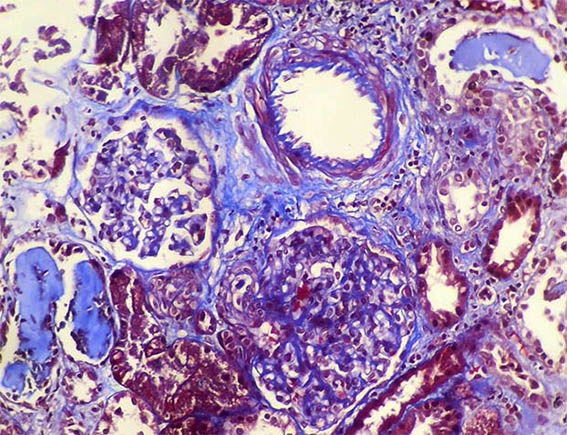

A 40-year-old man presented with severe acute liver failure secondary to hepatitis A virus infection, and acute kidney injury.

More relevant laboratory tests: thrombocytopenia (76,000), hyperbilirubinemia (7.1 mg/dL), transaminitis (1.830 U/L and 2.320 U/L), and elevated INR. Serum creatinine: 5.2 mg/dL, BUN: 78 mg/dL, proteinuria: 100 mg/dL, without microhematuria.

A kidney biopsy was performed. Look at the images.

Figure 3.

H&E, X200.

Figure 10. Masson's trichrome stain, X200.